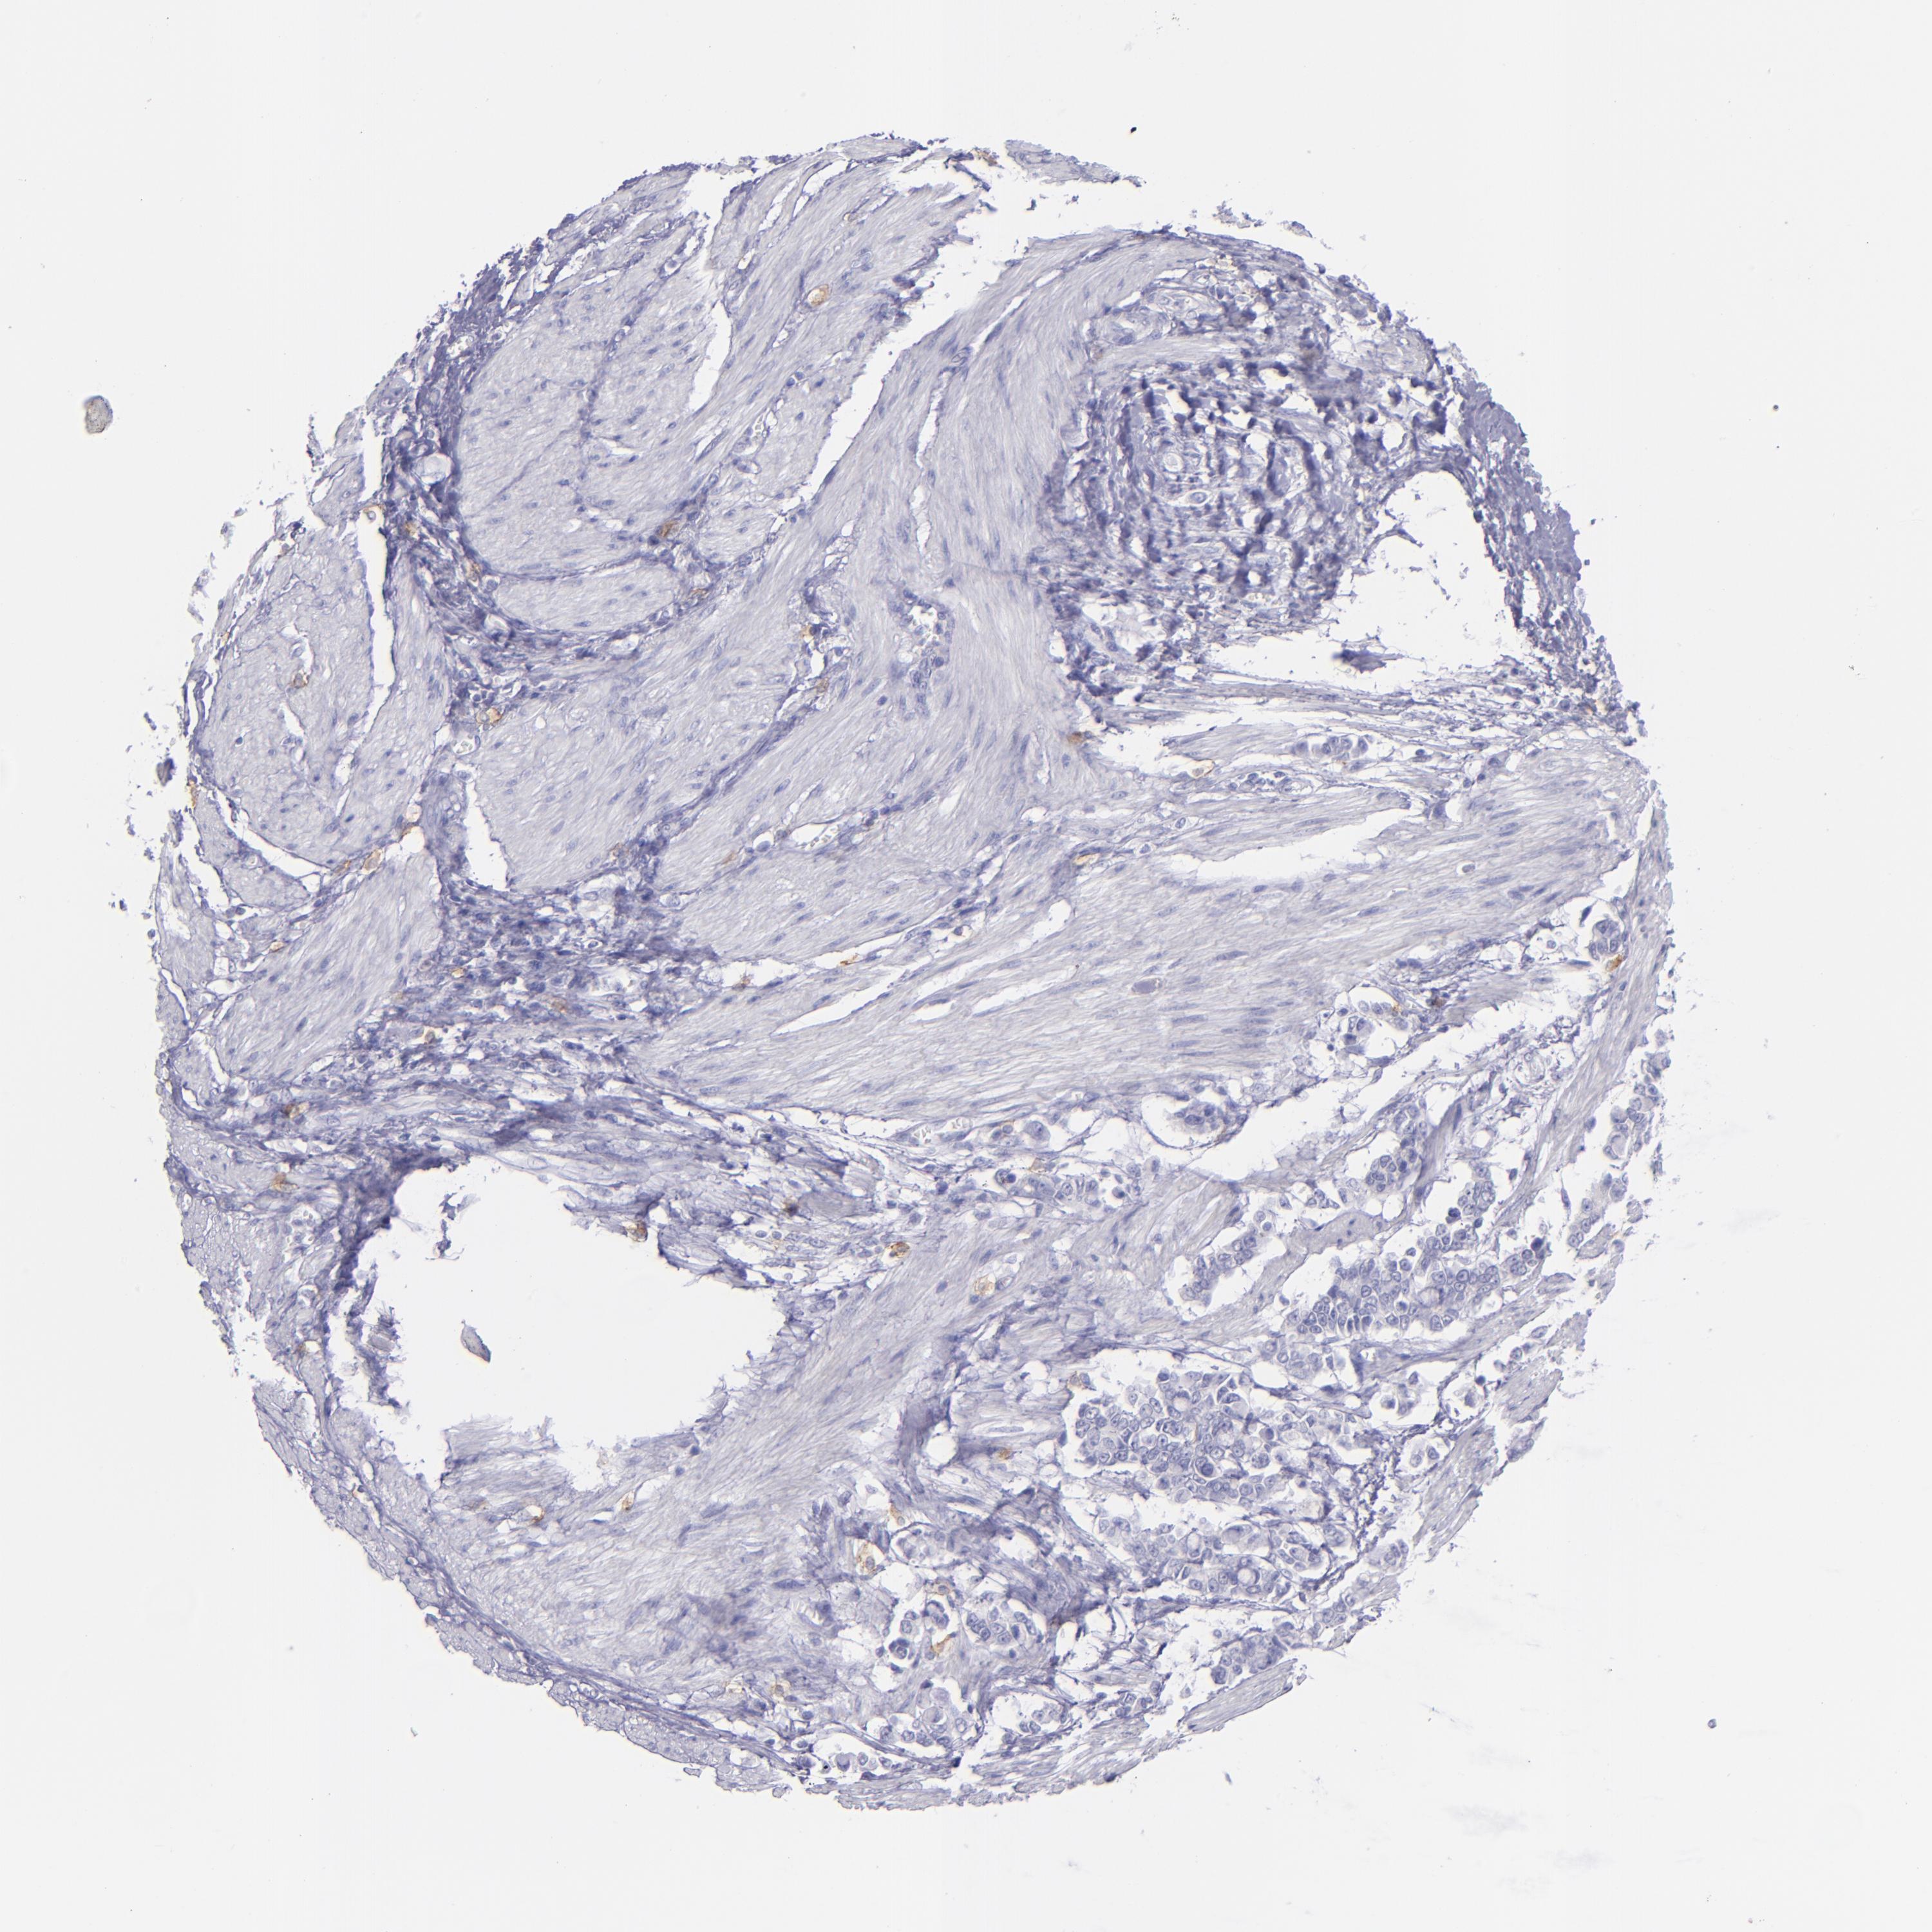

STOMACH CANCER - Protein expressioni

A mouse-over function shows sample information and annotation data. Click on an image to view it in a full screen mode. Samples can be filtered based on level of antibody staining by selecting one or several of the following categories: high, medium, low and not detected. The assay and annotation is described here.

Note that samples used for immunohistochemistry by the Human Protein Atlas do not correspond to samples in the TCGA dataset.

Antibody stainingi

Antibody staining in the annotated cell types in the current human tissue is reported as not detected, low, medium, or high, based on conventional immunohistochemistry profiling in selected tissues. This score is based on the combination of the staining intensity and fraction of stained cells.

Each image is clickable and will lead to virtual microscopy that enables deeper exploration of all samples and also displays staining intensity scores, fraction scores and subcellular localization as well as patient and tissue information for each sample.

Antibody HPA028900

Antibody CAB002508

Staining

High

Medium

Low

Not detected

Intensity

Strong

Moderate

Weak

Negative

Quantity

>75%

75%-25%

<25%

None

Location

Nuclear

Cytoplasmic/membranous

Cytoplasmic/membranous,nuclear

Adenocarcinoma, NOS